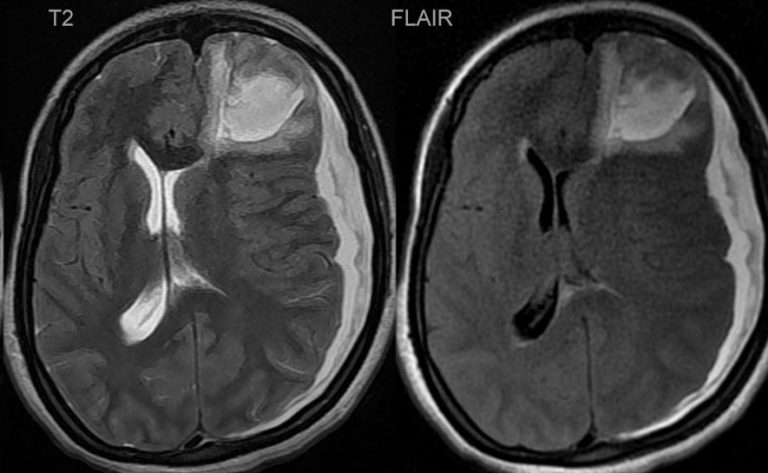

כיצד ניתן לאבחן דימום מוחי בוודאות?

אבחון ודאי של דימום מוחי מתבצע באמצעות הדמיה, בדרך כלל CT ראש ולעיתים MRI.

בדיקה קלינית תקינה אינה שוללת דימום. גם חבלה שנראית קלה עלולה להסתיר ממצא מסכן חיים.